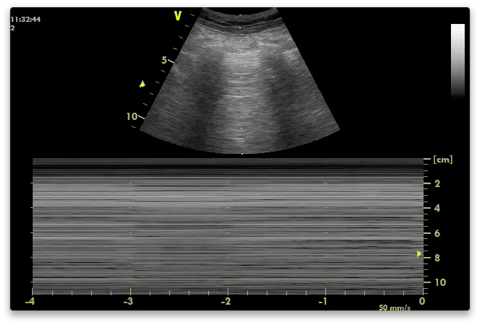

What is the seashore sign on M mode of lung ultrasound?

Seashore sign: non-moving chest wall appears as horizontal lines (ocean waves) and the sparkling artifact from lung sliding (ie. pleural movement) appears as a grainy pattern (sandy beach)

-demonstrates that the visceral pleura slides directly on the parietal pleura!

Seashore sign = on M mode, reflects normal lung sliding = the waves are the non-moving ribs/muscle/chest wall and the sandy beach are the artifacts generated by the movement of the pleura